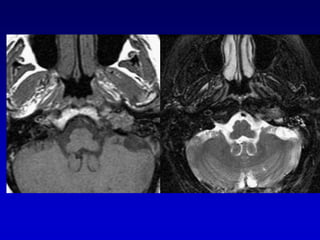

GLOMUS YUGULAR(paraganglioma)Erosion de la espina yugularInvasion hacia la caja timpánica

Caso 2TAC-RM